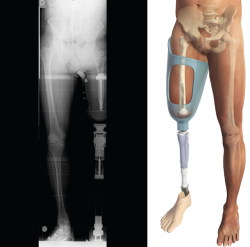

Siempre que la viabilidad de una amputación TT no sea posible, debemos considerar la DR antes que la amputación TF, donde la preservación de los cóndilos femorales facilita la adaptación de un encaje con apoyo distal del muñón (Figura 1). Clínicamente, el apoyo distal es la ventaja más importante en las DR con respecto a la amputación TF, ya que permite transferir directamente la carga distal al muñón femoral y, de este modo, aumentar la independencia en la marcha y reducir el consumo de oxígeno(6,7).

Figura 1. Desarticulación de rodilla.

Figura 5. Telemetría del implante Keep Walking® en el paciente protetizado donde se puede apreciar la alineación del encaje.

Las longitudes del vástago oscilan entre 120 y 180 mm, el diámetro de 11 a 17 mm y los diámetros de espaciador oscilan entre 54 y 62 mm. Finalmente, se monta el implante definitivo y se inserta impactado a press-fit en el fémur. Los tejidos blandos son suturados realizando una correcta mioplastia alrededor del espaciador (Figuras 4 y 5).